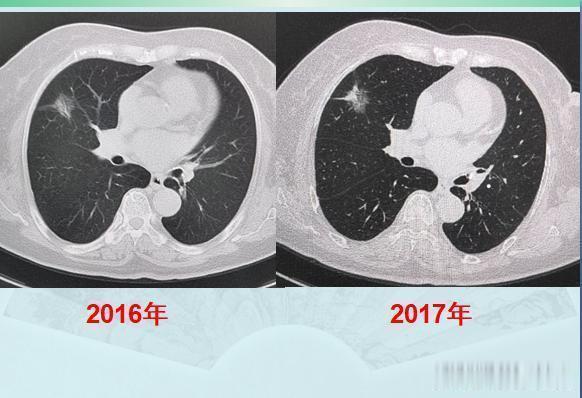

这位病人很不幸,得过乳腺癌,又得了肺癌,但她又很幸运,两次癌症都做了根治手术,尤其这个肺腺癌,中间拖了两年都没有转移,癌细胞相对很温柔!假如所有的癌症病人身上,都是这种慢吞吞的癌细胞就好了!很可惜,不是!第二位,胸痛2年,一直拖着这是一位69岁的男病人,常年吸烟,每天一包,两年前开始偶尔胸痛,能忍受,没有咳嗽咳痰咳血等其他症状,也就没当回事。最近一个月加重了,晚上需要吃止疼片才能顺利入睡,就过来做了肺CT,结果发现左肺长了一个像土豆一样圆滚滚的肿块:

增强CT显示肿块轻度不均匀强化,同时还发现了纵隔淋巴结肿大,符合肺癌,而且他已经没有手术机会了。同样是拖了两年,这位病人的运气就没有第一位老太太那么好!

后来老人做了经皮肺穿刺,病理是小细胞肺癌。实际上CT图像也提示小细胞肺癌的诊断:1.原发灶比较光滑,像土豆一样,可以有浅分叶,血供不丰富所以轻度强化;2.小细胞肺癌对血管破坏比鳞癌轻,很少发生大片坏死,所以空洞少见;3.小细胞肺癌转移早,原发灶较小时就常见肺门及纵隔淋巴结多发转移,从而失去手术机会;4.与吸烟关系密切。不过幸运的是,这位老人的肺癌对化疗很敏感,做了两个周期的化疗(依托泊苷+奈达铂)后复查,病灶明显缩小,纵隔淋巴结也萎缩了: